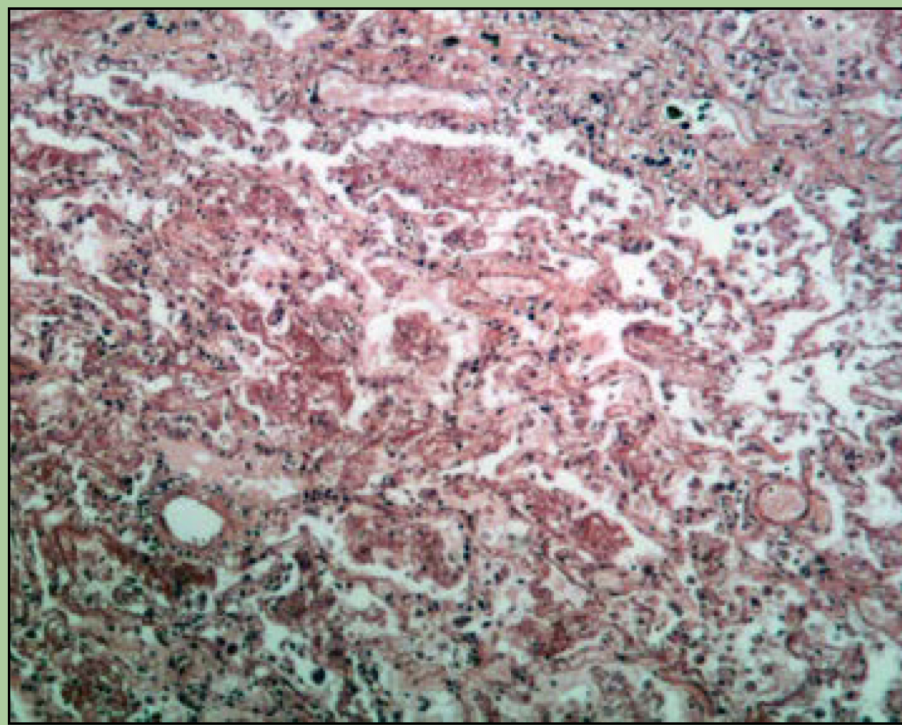

New cards

What disorder is this?

Emphysema

COPD

breakage and collapse of alveoli

95

Pneumonia

inflammatory disease

96

Tuberculosis

mycobacterium tuberculosis

97

Lung carcinoma

primary lung cancer

98